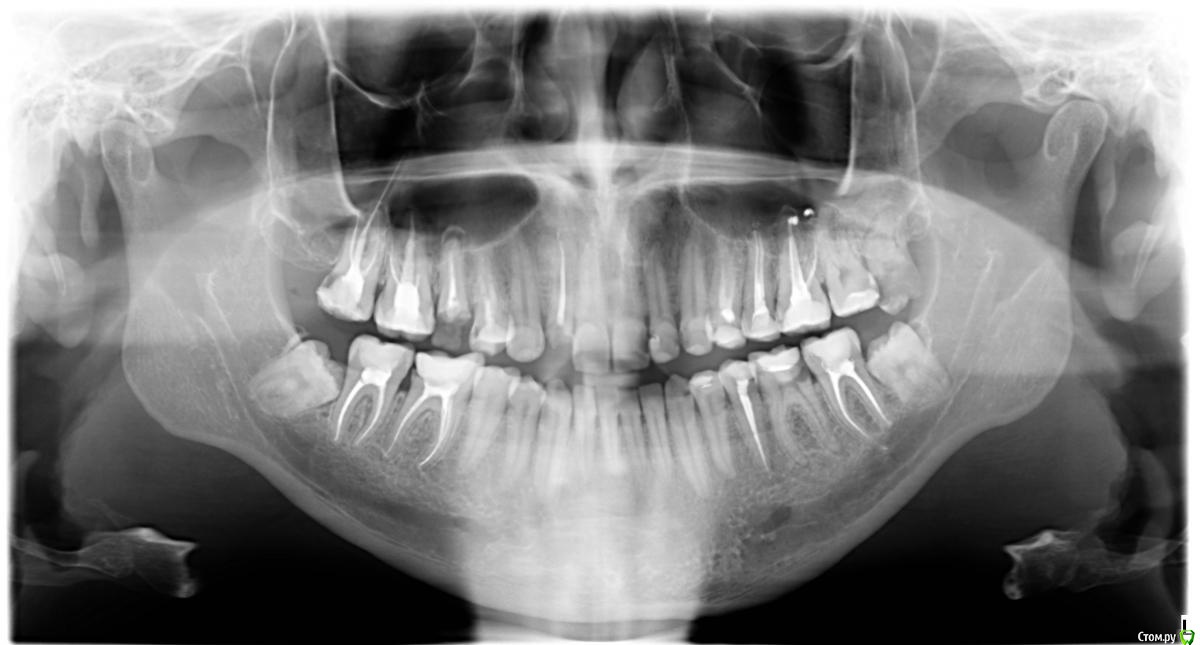

b.wtcc Опубликовано 7 декабря, 2016 Поделиться Опубликовано 7 декабря, 2016 Здравствуйте.Обращался в стоматологию. Лечили, лечили...сказали все готово.Но остались вопросы, по зубам которые не тронули. верхние левые 4, 6, 7верхняя правая 4низ право 7нижние 8ки сказали пока не трогатьнижние центральные начали немного зудеть, не постоянно Снимок до лечения. Подскажите как дальше быть. Ссылка на комментарий

b.wtcc Опубликовано 7 декабря, 2016 Автор Поделиться Опубликовано 7 декабря, 2016 Нет, это снимок до лечение. Хочу на днях сделать новый - как бы там вопросов не прибавилось ... Ссылка на комментарий